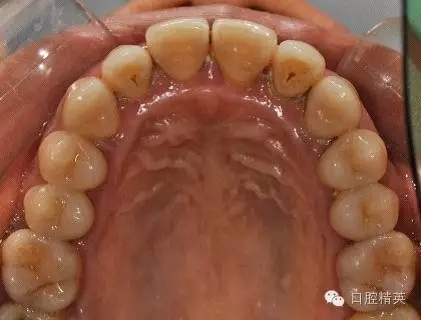

本病例 :女 34歲,主訴刷牙出血,覺(jué)牙齒輕度松動(dòng)一年。

檢查見(jiàn)大量齦上及齦下結(jié)石,探診出血,牙周袋較深,32-42 II度松動(dòng)。X線片顯示牙槽骨水平吸收。

診斷:成人慢性廣泛性中度牙周炎。

治療前: